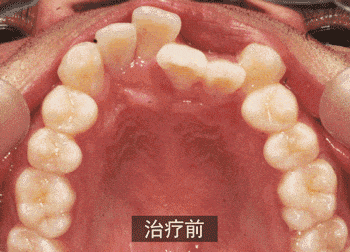

如果你的牙齿过于拥挤、前突,很有可能需要拔牙,这是为了给牙齿排齐、内收留有足够的空间。